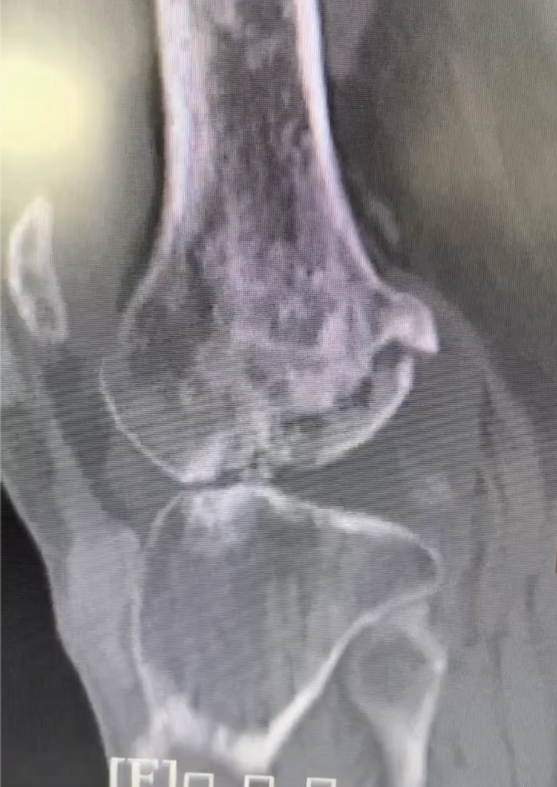

影像显示,患者骨质中布满痛风石,全关节破坏且有部分骨质缺损。

据悉,43岁的梁先生痛风多年,长年忍受关节疼痛困扰。近一年,梁先生感觉膝关节疼痛越发严重,且活动受限,9个月前,他甚至只能依靠双拐行走,完全丧失劳动能力。今年2月,梁先生来到南医三院关节外科就诊,影像学检查显示,梁先生全身多处痛风石,尤其是膝关节布满大量痛风石,已严重侵蚀骨质,导致膝关节不稳和功能障碍。对于像梁先生这样晚期痛风性关节炎合并骨质破坏和关节不稳的患者,单纯的药物治疗难以恢复行走能力,关节外科会同多学科会诊,计划为梁先生实施全膝关节表面置换手术。